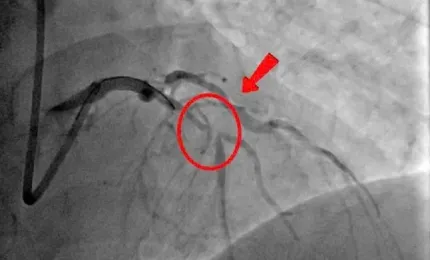

TPO - Đang đi khám vì cơn đau ngực kéo dài, người đàn ông 46 tuổi bất ngờ lên cơn nhồi máu cơ tim cấp ngay tại bệnh v